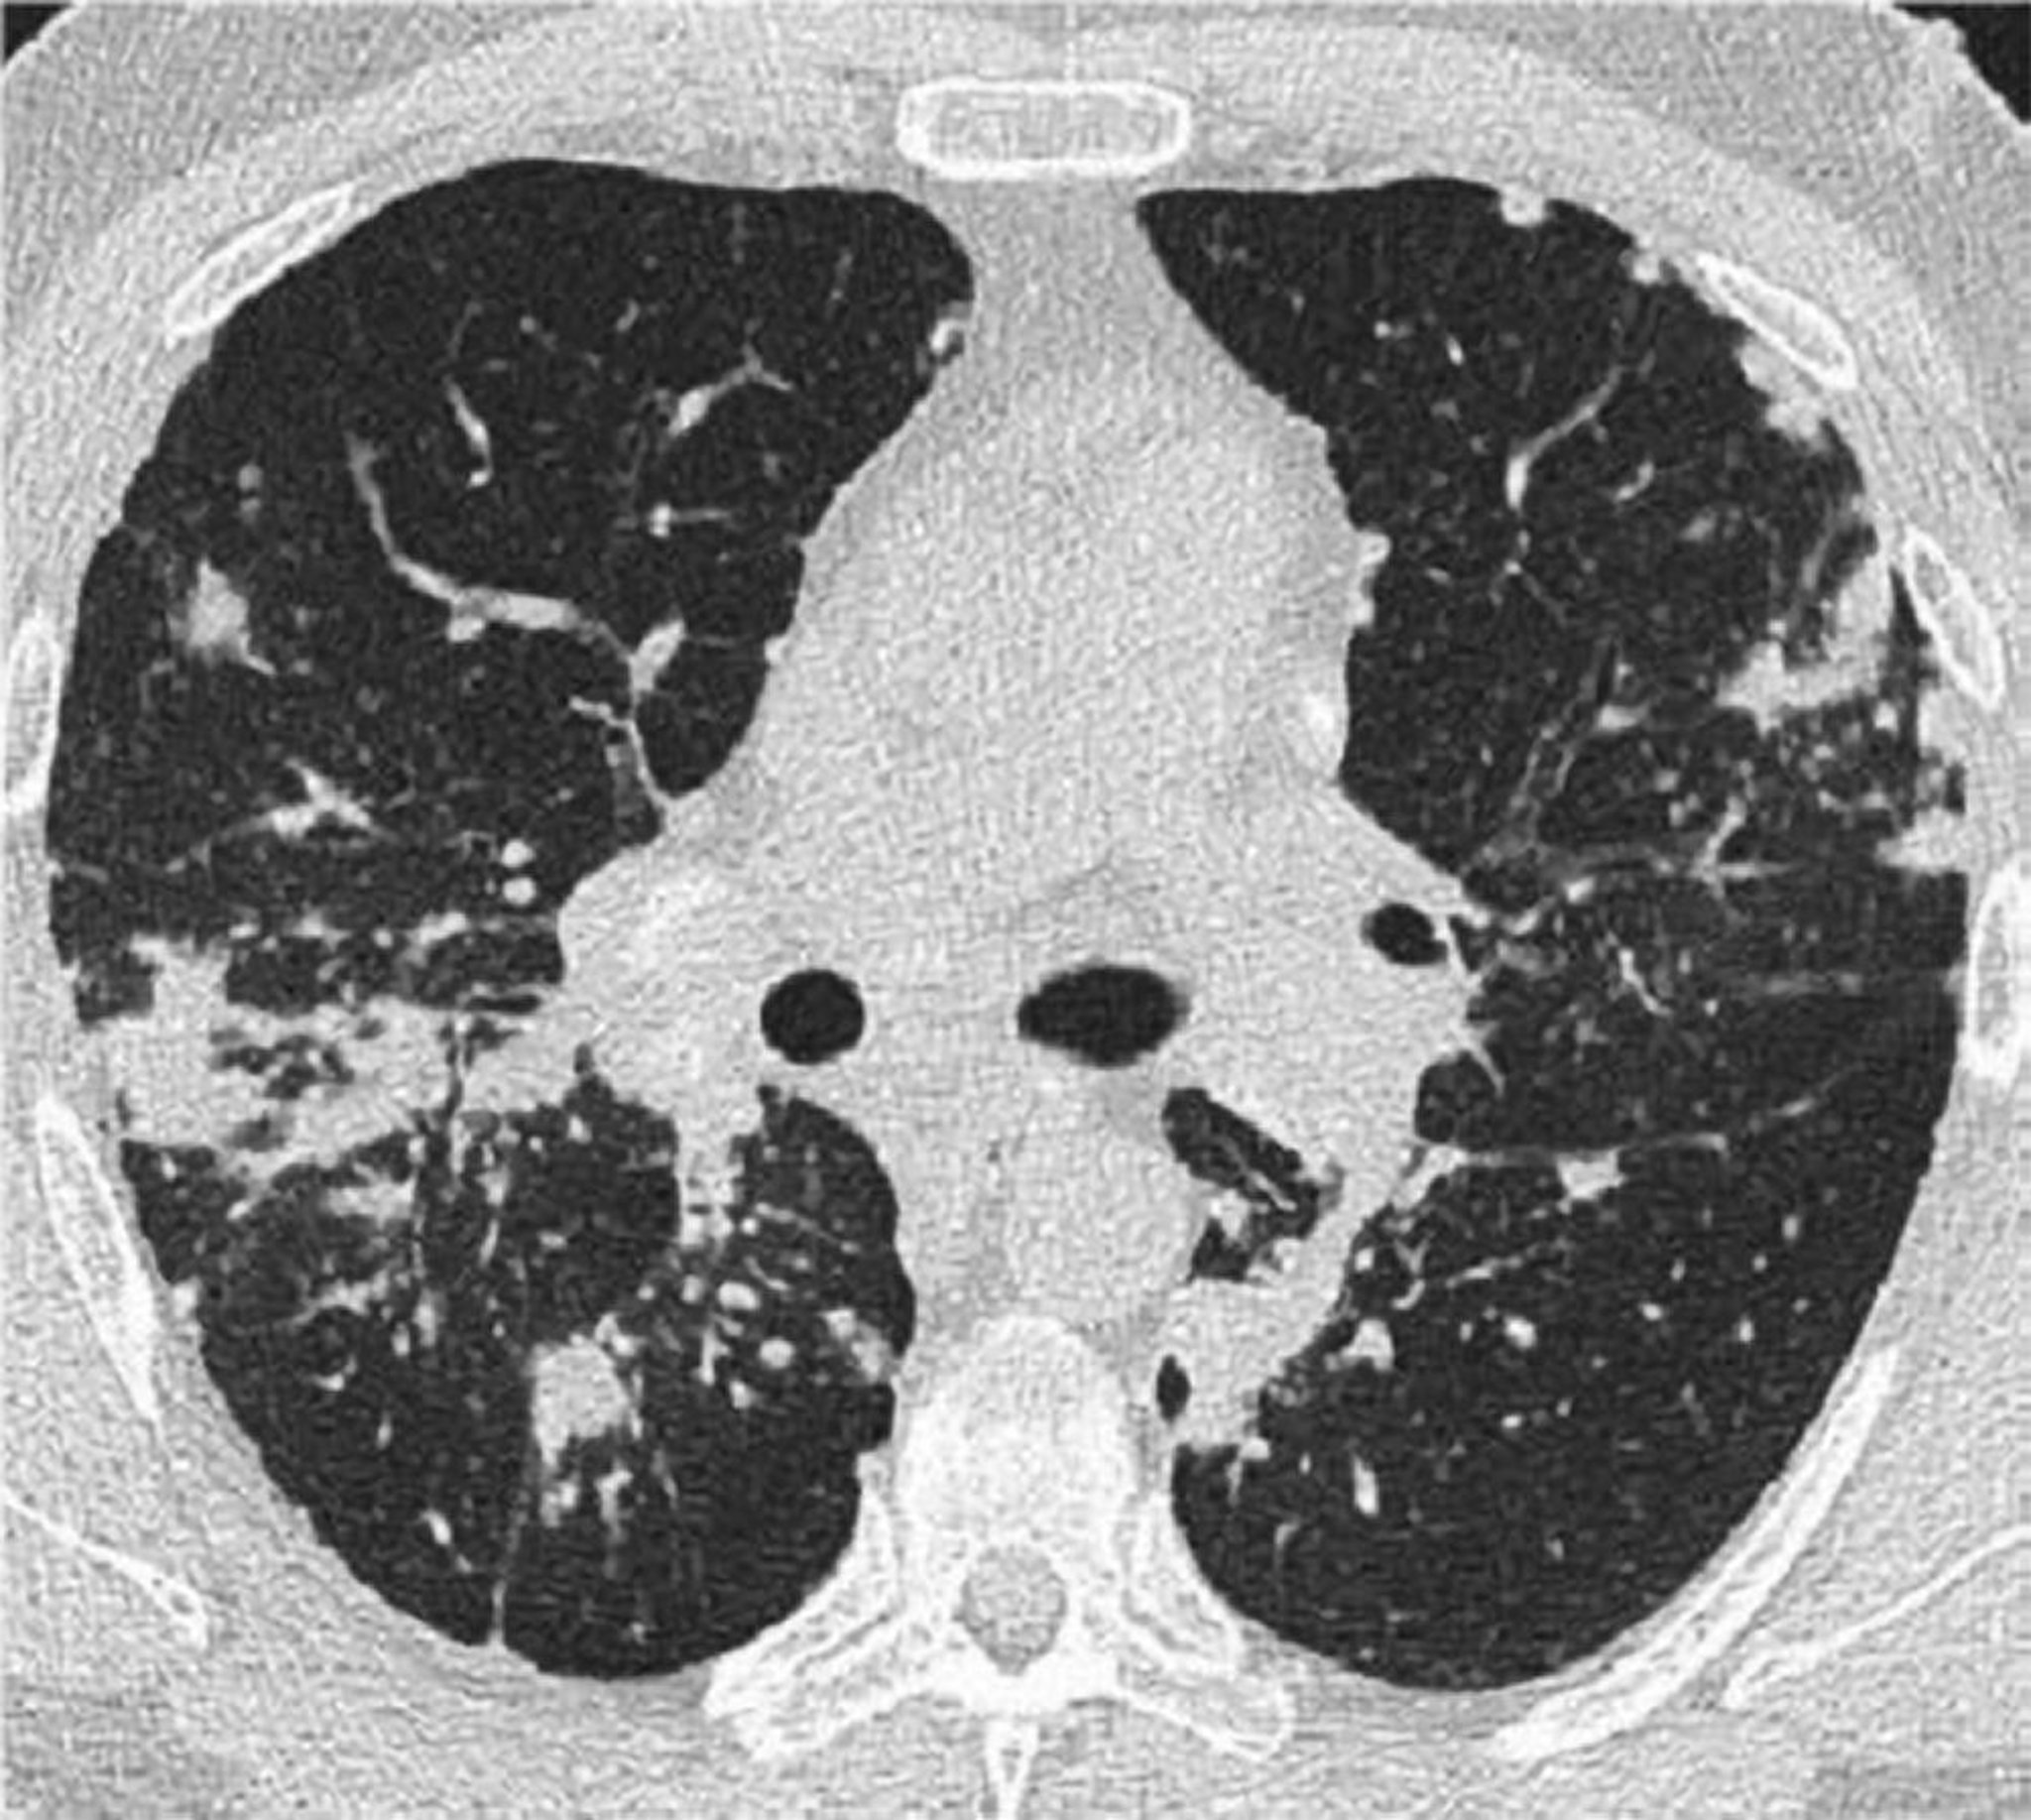

Thorax-CT-Scan bei pulmonaler Sarkoidose

Dieses hochauflösende CT des Thorax eines Patienten mit pulmonaler Sarkoidose zeigt eine Verdickung der bronchovaskulären Bündel und Perlenbildung der interlobulären Septen.

Image courtesy of Birendra P. Sah, MD, FCCP.